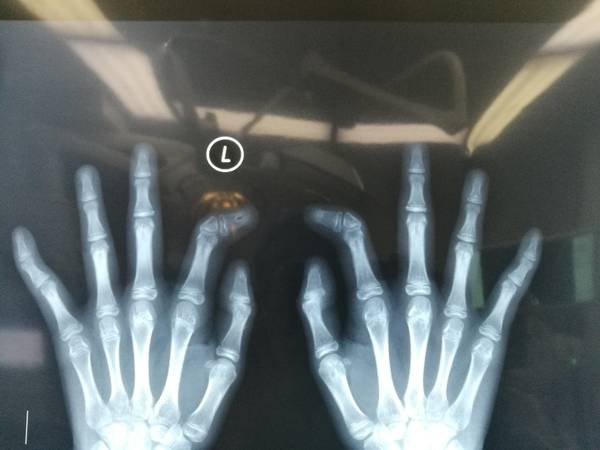

腕关节病人

关节功能评定

陈山林主任的学生刘璐博士在评估腕关节功能